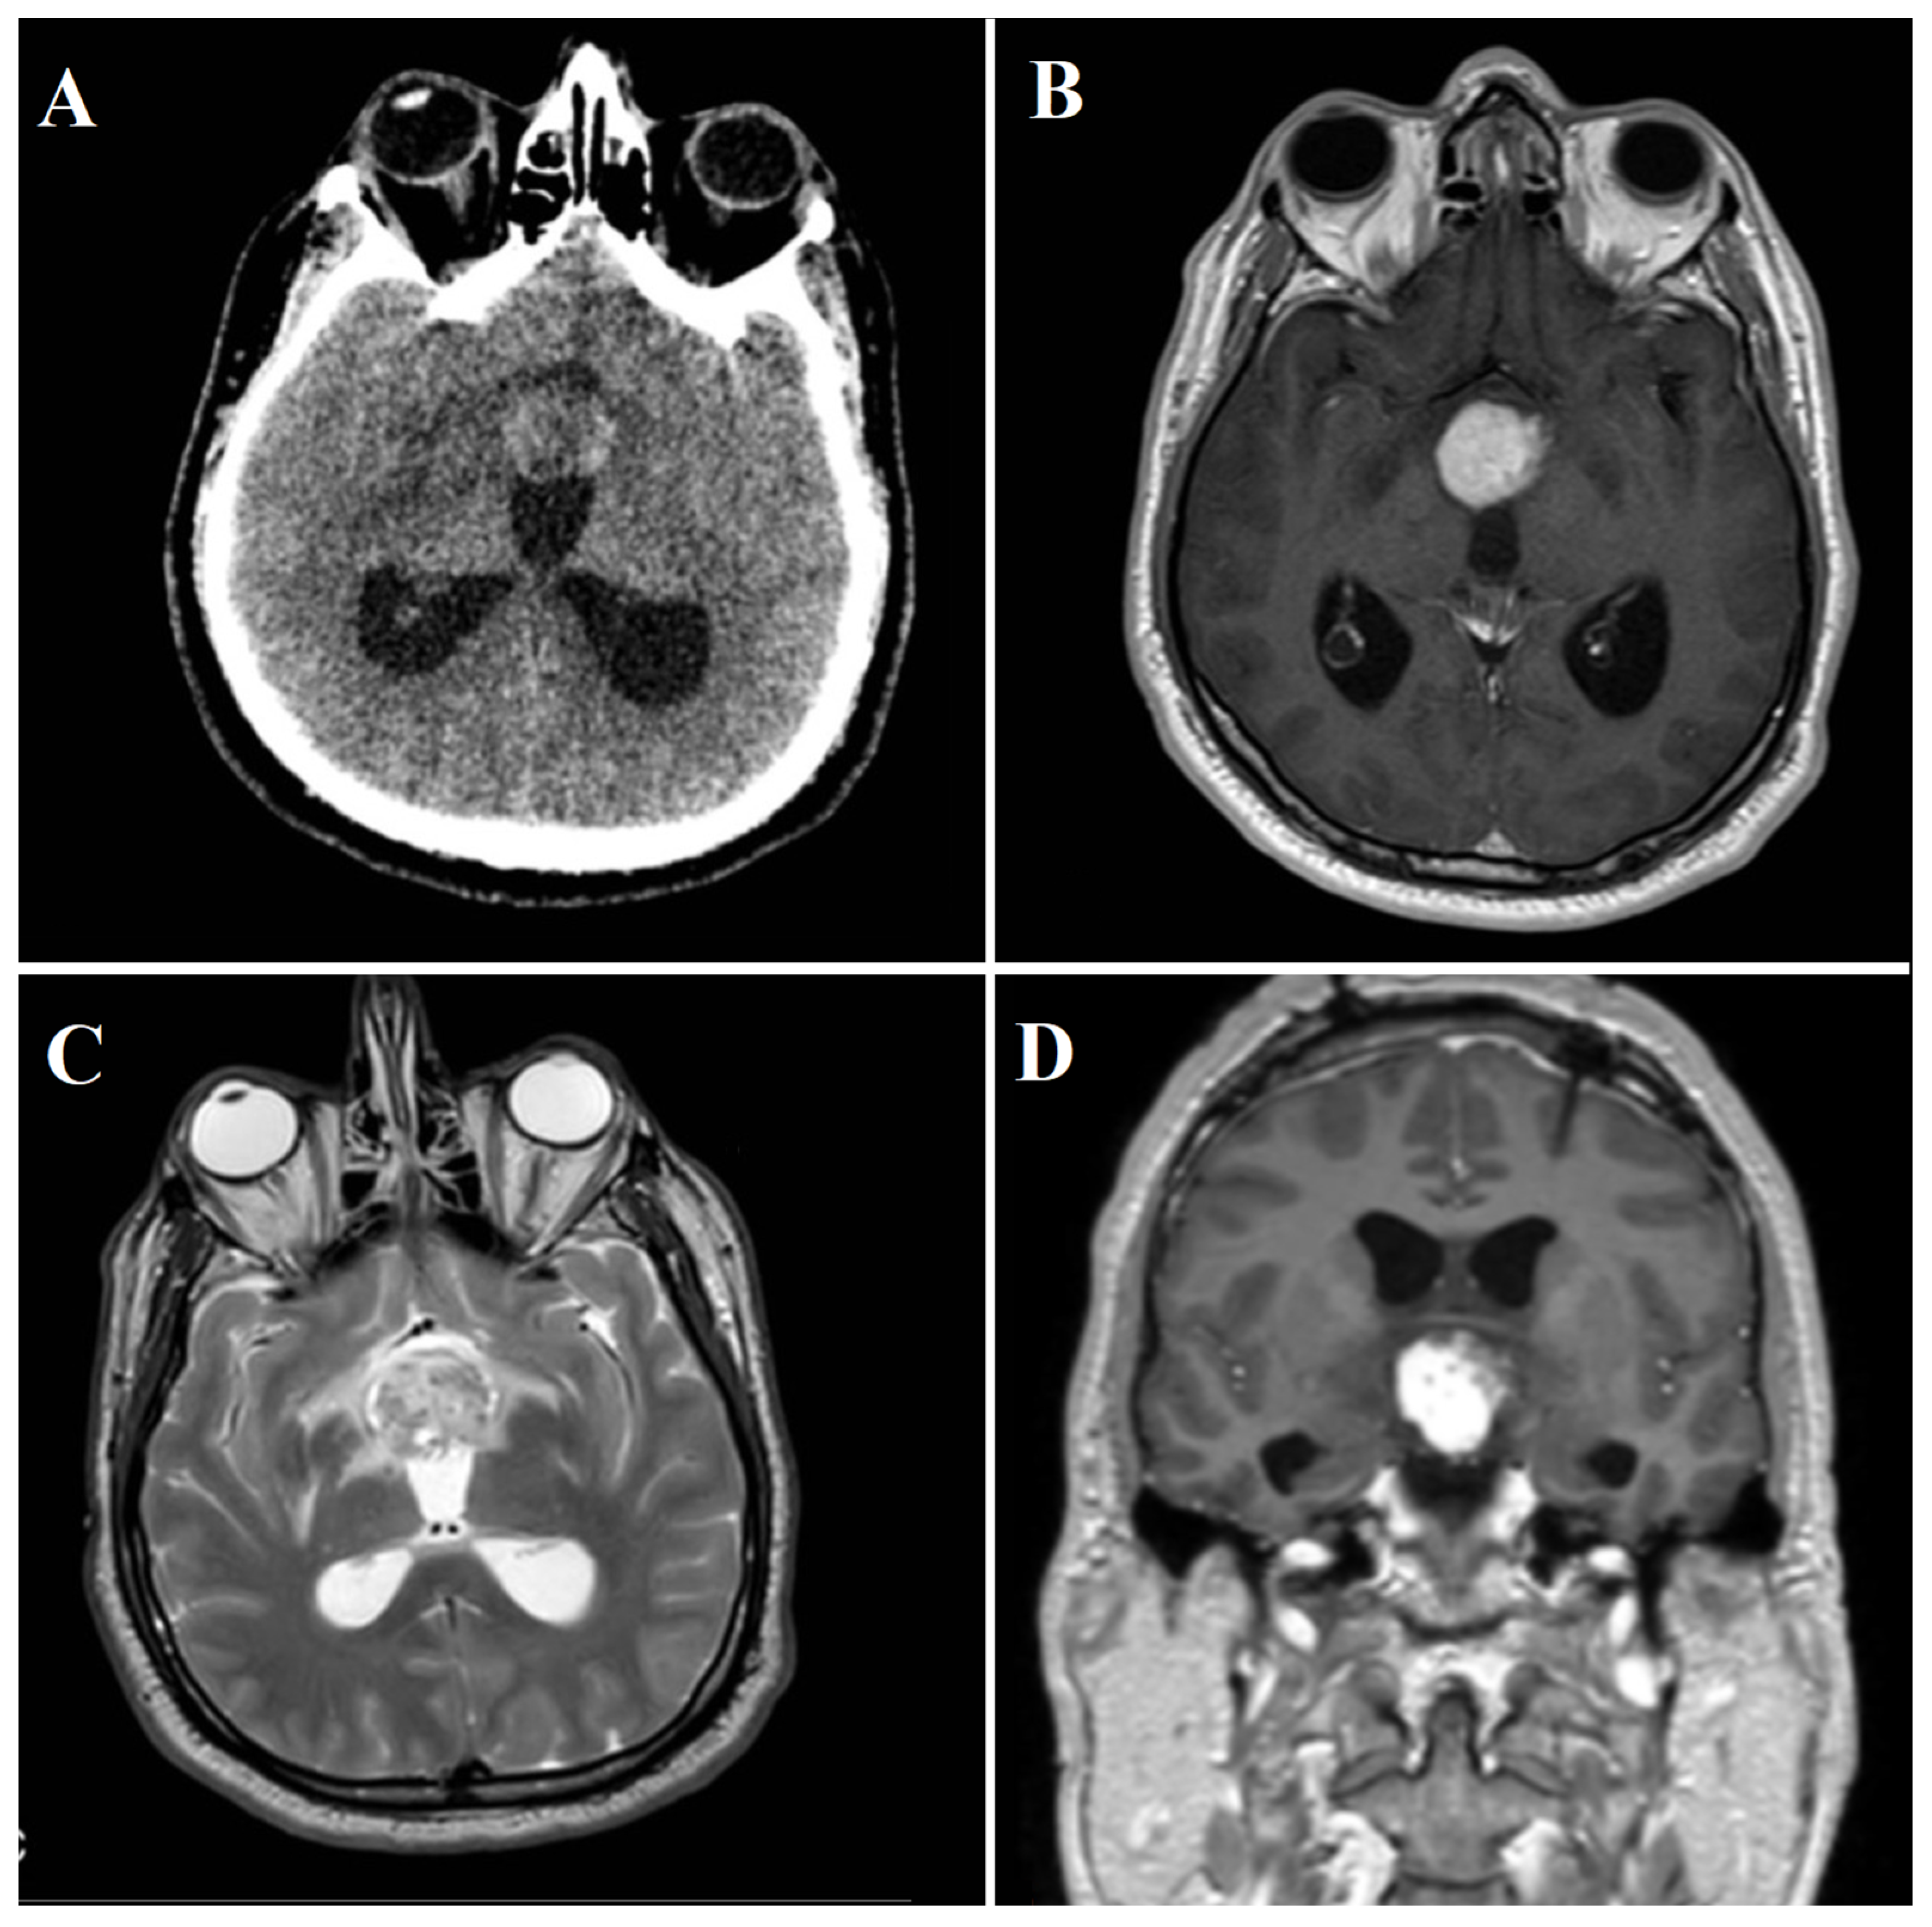

3.2.2. Radiological Findings

| Present case | / | 48 | Male | Third nerve palsy, stuporous state | Gross total | SWI_sequences with intralesional bleeding, microcalcification. Post-contrast administration revealed intense enhancement and increased perfusion indexes | Transient DI, hypopituitarism | 1 year | Transcranial |